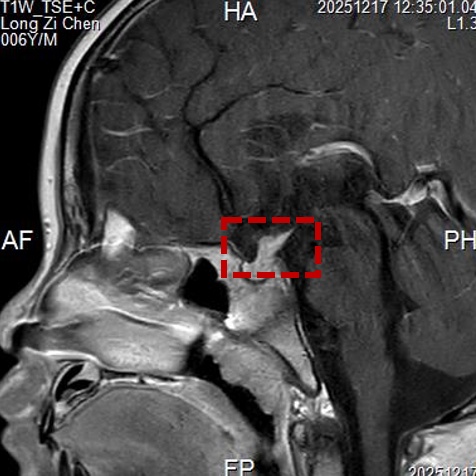

为了明确诊断,必须获取病变的垂体柄组织进行病理分析。但儿童脑部手术风险极高,如何在精准取到活检组织的同时,最大限度地保护孩子的大脑功能、减少创伤?张晨冉主任团队给出了一个精妙的答案:眉弓锁孔入路手术。

该手术切口并不在头顶部,而是巧妙地隐藏在孩子的右侧眉毛里,长度仅约4厘米左右。医生通过这个“钥匙孔”大小的骨窗,借助显微镜和神经内镜的辅助,精准地抵达脑深部的鞍区。术中,医生在显微镜下清晰地分辨出视神经、颈内动脉等重要结构,并在增粗的垂体柄上小心翼翼地钳取了数块组织送检。术中冰冻病理结果提示“朗格汉斯细胞组织细胞增生症待定”。由于这类肿瘤对化疗敏感,为了避免过度切除对患儿造成不必要的神经功能损伤,手术团队果断决定,在明确病理后终止切除,将主要任务锁定在“精准活检”。整个手术过程顺利,出血极少。术后,小晨被安全送回监护室病房。